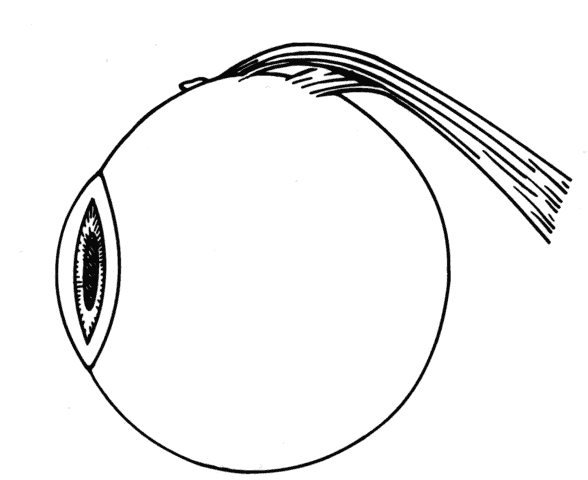

Whenever possible, efforts should be made to obtain information from the patient's history and from clinical records regarding the original diagnosis, preoperative measurements, and previous surgical procedures. In lieu of this information, some information can be obtained on examination. For example, slit lamp examination may disclose conjunctival scarring, which may suggest which muscles have had prior surgery (Fig. 7).

Fig. 7. Conjunctival scarring over the lateral rectus muscle and the history of correction of an exotropia suggest that the lateral rectus muscle had been recessed.